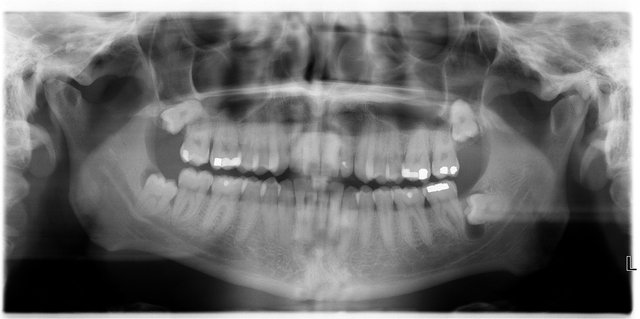

Panorama-Übersichtsaufnahme

Gekrümmte Wurzeln beim Nervenkanal

Wurzelreste beim Nevenkanal

Wurzelreste beim Nervenkanal